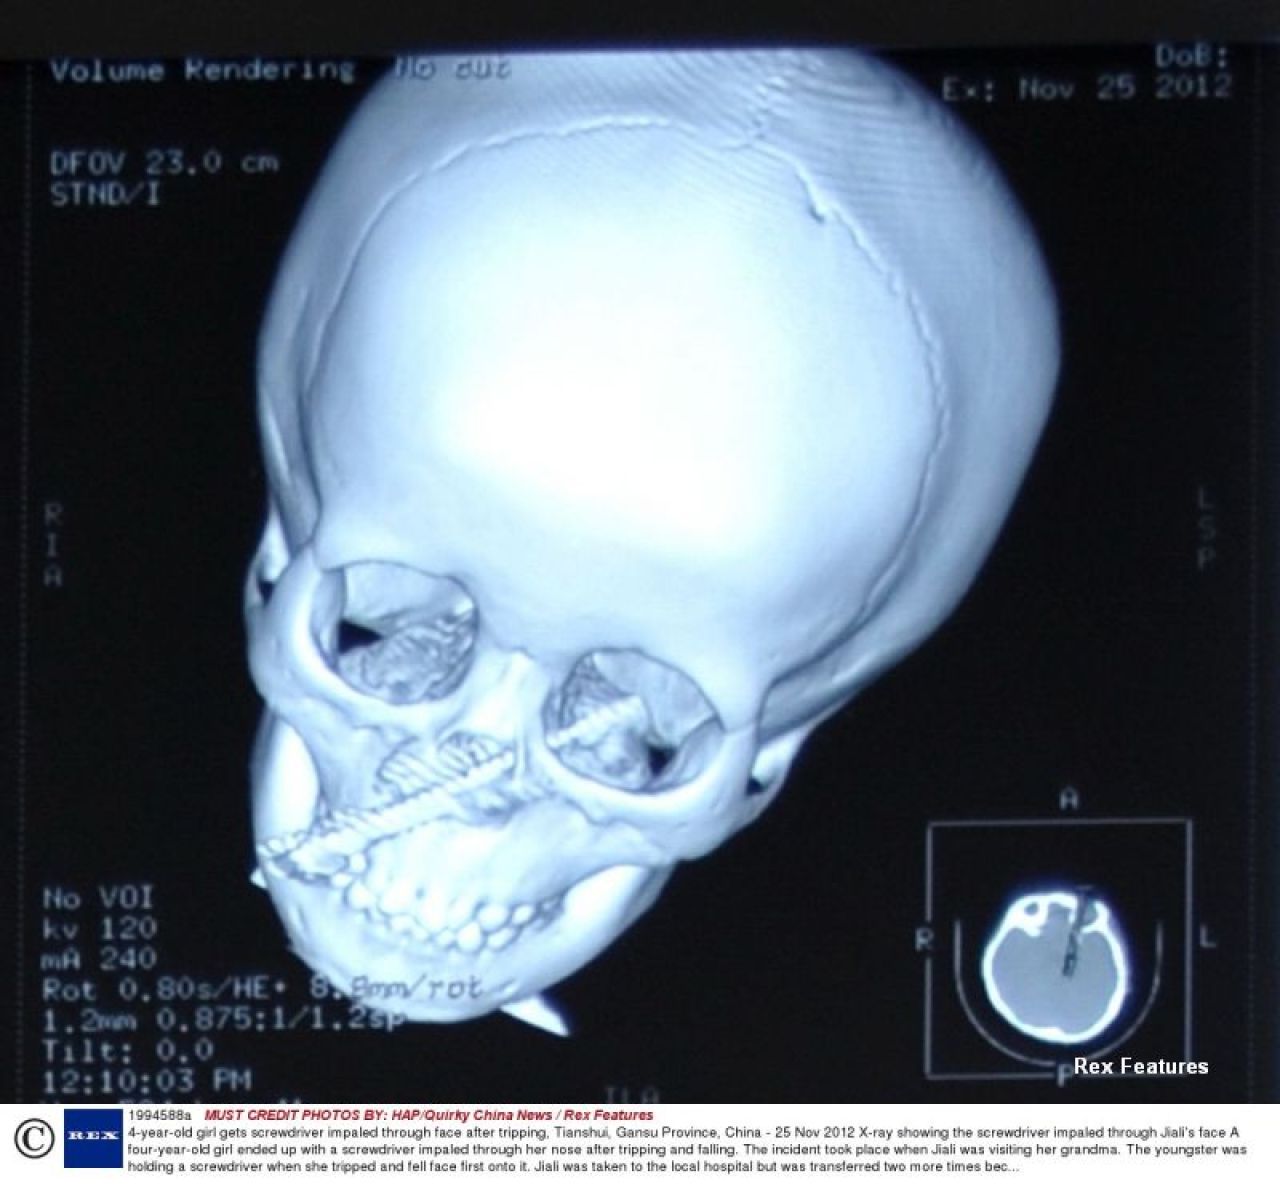

IMAGINI SOCANTE. O fetita de 4 ani a supravietuit miraculos dupa ce i-a intrat o surubelnita in fata

Jiali Gang, o fetita care traieste in provincia chineza Gansu, a reusit sa scape cu viata dupa ce, in urma unui accident, o surubelnita i s-a infipt in fata.

Conform Mirror, Jiali se juca acasa la bunica ei cu unealta, iar la un moment dat s-a impiedicat si a cazut cu fata in ea.

Surubelnita i-a patruns prin nas si s-a oprit la doar 2 milimetri de creier.